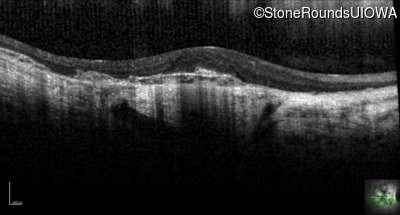

Optical Coherence Tomography - Right - 20/100 -2

Exemplar / OCT Stack